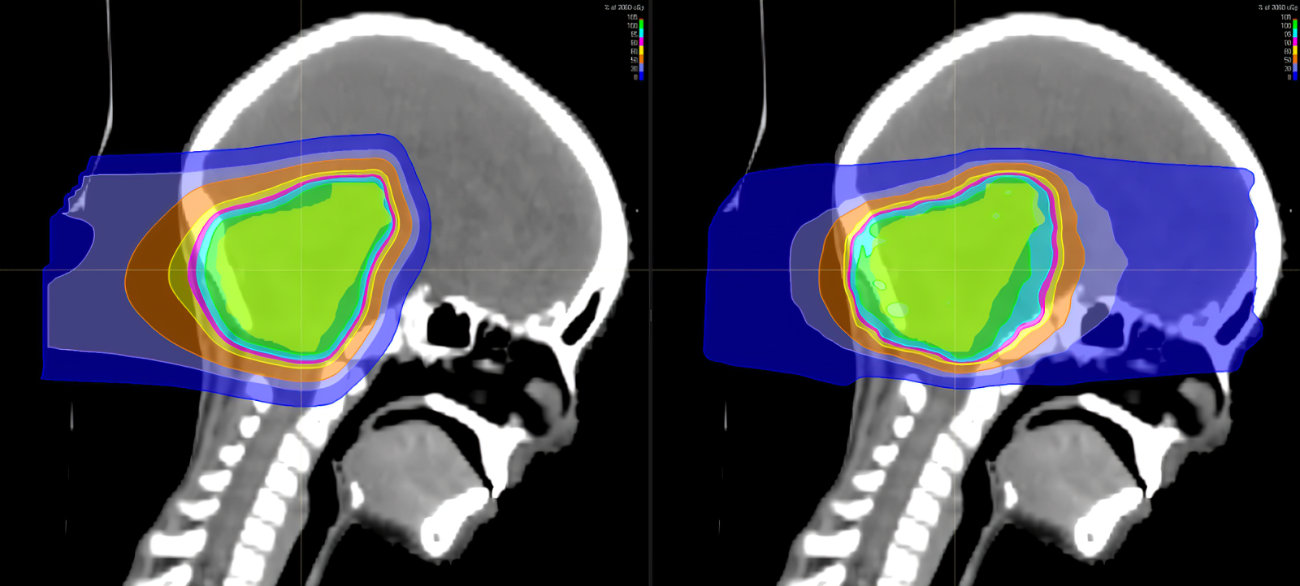

脑癌最为常见类型是髓母细胞瘤,是中枢神经系统恶性程度最高的神经上皮性肿瘤之一。绝大多数生长在第四脑室顶之上的小脑蚓部,儿童是主要的患病人群。  各年龄段发病率  髓母细胞瘤好发于儿童,尤其男性多见。在...【全文】